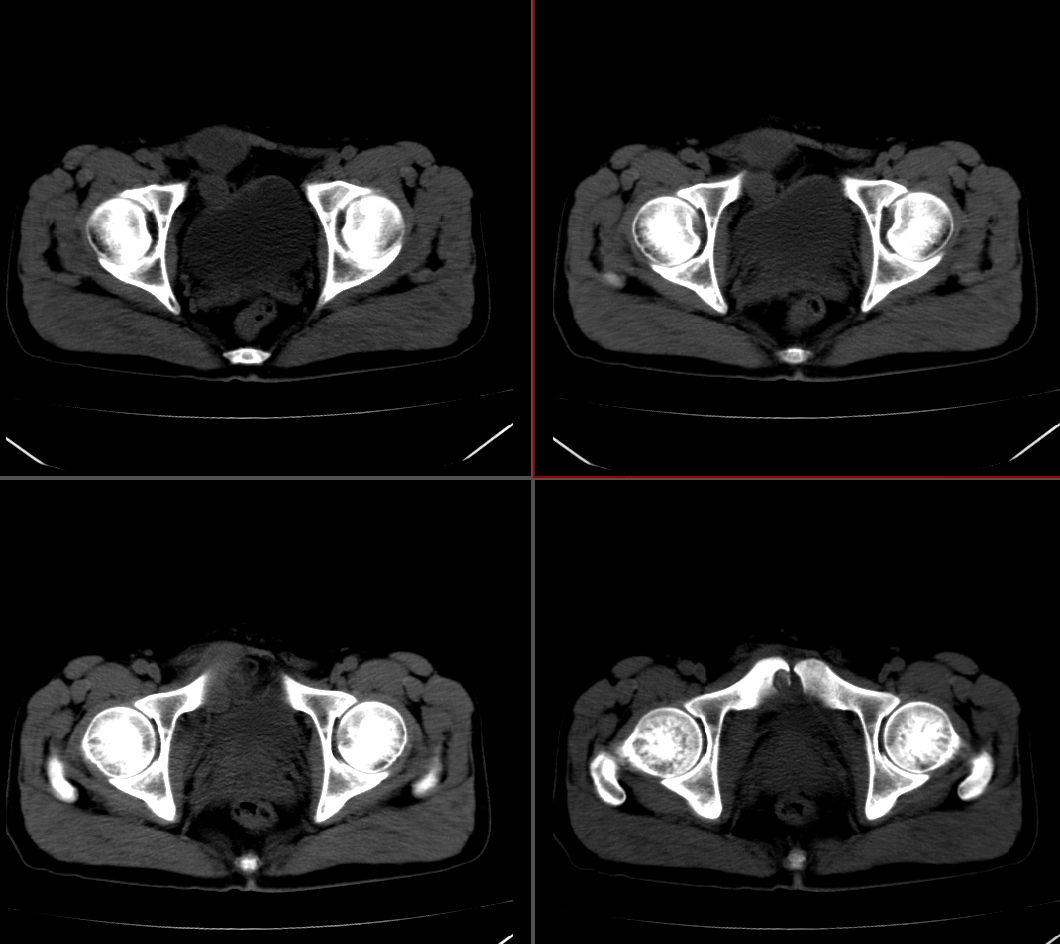

右腹直肌腱鞘来源,韧带样纤维瘤可能性大,病变有侵袭性,右侧耻骨联合有骨质缺损。

前腹壁肿块,囊性变,右侧耻骨联合有骨质缺损。

考虑神经源性肿瘤,神经鞘瘤

右腹直肌腱鞘来源,耻骨联合有骨质缺损,考虑神经源性肿瘤

考虑 1脐尿管囊肿 2神经鞘瘤囊变。

右腹直肌腱鞘来源-腱鞘囊肿?神经源性肿瘤?

支持:右腹直肌腱鞘来源-腱鞘囊肿?神经源性肿瘤?